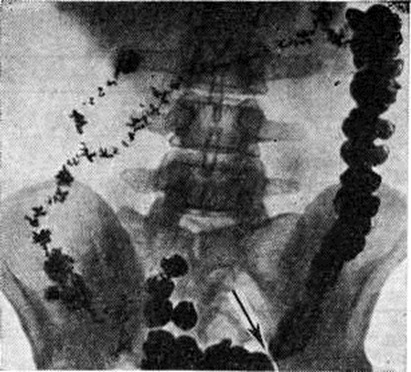

ДиагнозДиагноз устанавливают обычно на основании анамнеза и жалоб больного. Важно выяснение этиологии и типа Запоры, особенно своевременное распознавание опухолевых процессов, вызывающих механический Запоры; при этом наряду с клинический, данными (пожилой возраст, недавнее начало Запоры у лиц с нормальным стулом, примесь крови в кале и другие) большое, диагностическое значение приобретает рентгенологическое исследование, колоноскопия (смотри полный свод знаний), ректор оманоскопия (смотри полный свод знаний). При ректороманоскопии в случае гипермоторики слизистая оболочка прямой и сигмовидной кишок влажная, видна перистальтика, спазмы, окраска слизистой оболочки меняется быстро, при гипомоторике — слизистая оболочка сухая, тусклая, дистальный отдел толстой кишки в спавшемся состоянии, продвижение тубуса затруднено. Известные трудности возникают при дифференциации воспалительных Запоры при колитах и Запоры преимущественно функциональной природы. Распознаванию природы и дифференциации Запоры способствует копрологические исследование (смотри полный свод знаний Кал), биопсия слизистой оболочки прямой или сигмовидной кишки. Большое значение имеет определение типа моторных нарушений толстой кишки. Некоторые данные могут быть получены при пальпации: при преимущественно гипермоторных нарушениях дистальных отделов толстой кишки сигмовидная кишка спастически сокращена, при гипомоторных нарушениях она может быть растянута, не перистальтирует. Важную информацию даёт запись моторики кишечника баллонотензографическим методом. Рентгенологическое исследование имеет целью выявить нарушения моторной функции и тонуса толстой кишки, первичный или вторичный Запоры Его проводят спустя определённые промежутки времени после приёма внутрь бариевой взвеси — через 4— 6—9—12—24—48 часов и позже. Основное внимание обращают на характер заполнения и опорожнения кишки, пассажа по ней бария, вид гаустр, наличие спастических сокращений, а также скоплений газа и жидкости. К ирригоскопии (смотри полный свод знаний) прибегают в случаях, когда необходимо исключить аномалию развития кишки или её органическое поражение, при которых Запоры (вторичный) может быть симптомом заболевания. При первичных Запоры обычно обнаруживают снижение моторной функции, повышение, или понижение тонуса кишки. Эти изменения могут распространяться на всю кишку или на отдельные её сегменты (рисунок 1). Рельеф слизистой оболочки имеет нормальный или несколько «раздражённый» характер (ирритационный рельеф): складки приподняты, расположены более продольно или поперечно, но лишены, признаков воспаления. Смещаемость кишки не нарушена. При гиперкинетических Запоры замедление пассажа бария сочетается с регионарным спазмом и глубокой, нередко сегментирующей гаустрацией в виде многочисленных перетяжек (рисунок 2). Спазмированный отдел кишки иногда имеет вид тонкого шнура (рисунок 3). Реже, при атонических Запоры, обнаруживают пониженный тонус всей толстой кишки или отдельных её сегментов, сопровождающийся расширением просвета, поверхностной сглаженной гаустрацией.